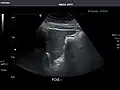

Abdominal Ultrasound (Full Exam)

STRUCTURED REPORT

(Technique: Transabdominal ultrasonography; Device: Toshiba Aplio XG)

Liver: Diffusely homogeneous and normal in echogenicity. No focal mass or contour nodularity. No intrahepatic biliary ductal dilatation.

Portal Vein: Patent main portal vein.

Gallbladder: No stones, wall thickening, or pericholecystic fluid.

Common Bile Duct: Nondilated measuring 1.3 mm at the level of the porta hepatis.

Pancreas: Visualized portions unremarkable.

Spleen: Normal in size.

Kidneys: Right and left kidneys measure 11.5 cm and 12 cm in length respectively. No hydronephrosis. Small left lower pole kidney cyst.

Ascites: None.

Aorta: Visualized portions normal in caliber, 16 x 15 mm.

IVC: Normal.

IMPRESSION:

Normal abdominal ultrasound.

Right kidney -